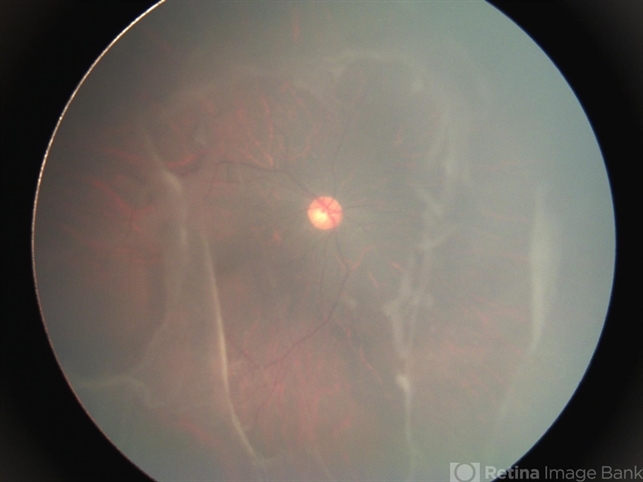

- vitreoretinal degeneration, Stickler Syndrome

- Fundus photograph of a 13-year-old male with Stickler Syndrome.